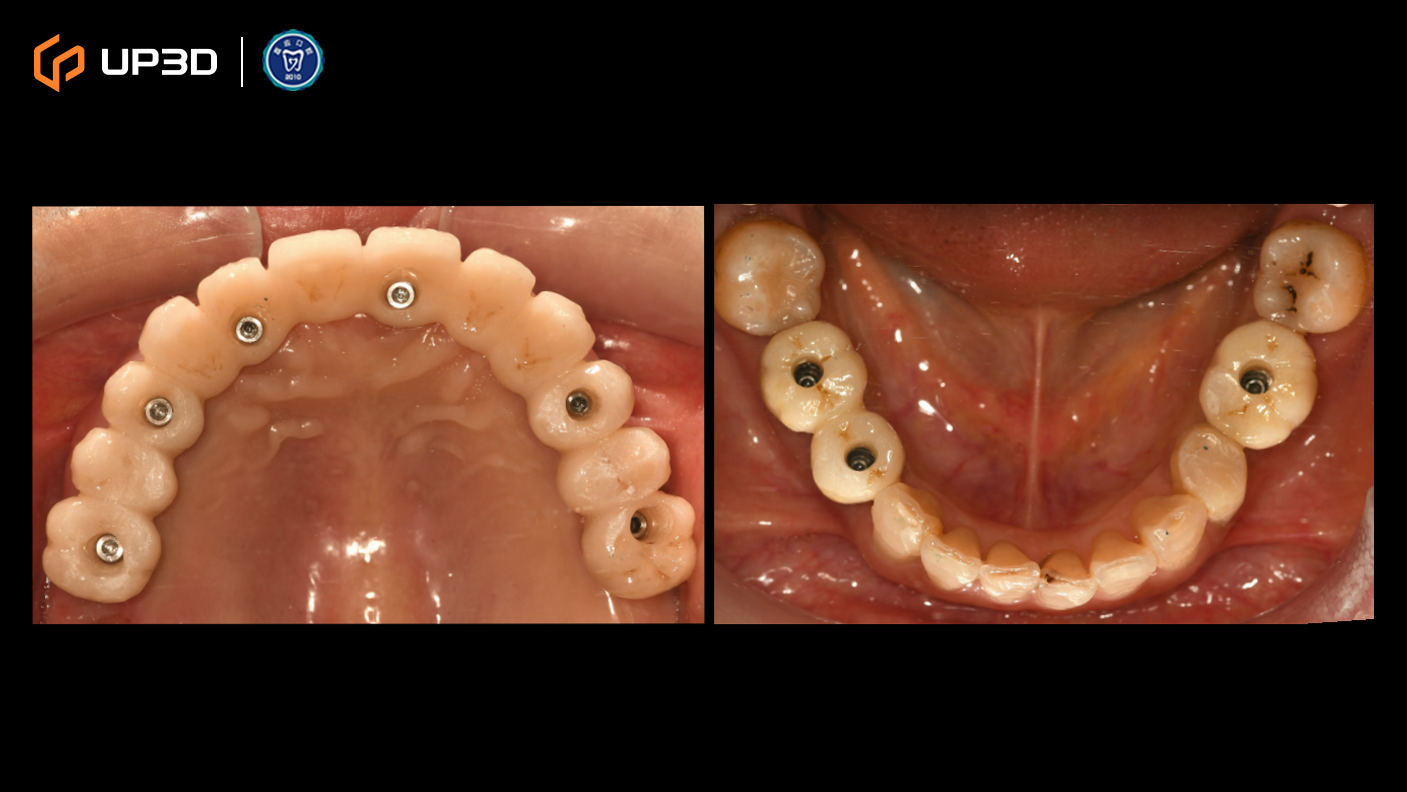

2.1 Intraoral Findings and Intraoral Scan Assessment

A digital intraoral scan (IOS) was used to capture maxillary and mandibular models. Clinical findings included multiple missing teeth, disordered dentition, and occlusal collapse with reduced facial support. Bone volume was limited in certain regions. The 3D scan clearly presented tooth morphology, soft tissue contours, and occlusal relationships—providing accurate data for subsequent digital implant planning.

4.1 Scan Body Placement

After implant placement, scan bodies were installed to ensure accurate transfer of implant positions to the digital workflow.

4.2 Intraoral Scanning (Digital Impression)

Intraoral scanning was performed chairside to capture soft tissue contours and implant positions, providing the dataset for designing an immediate provisional restoration.